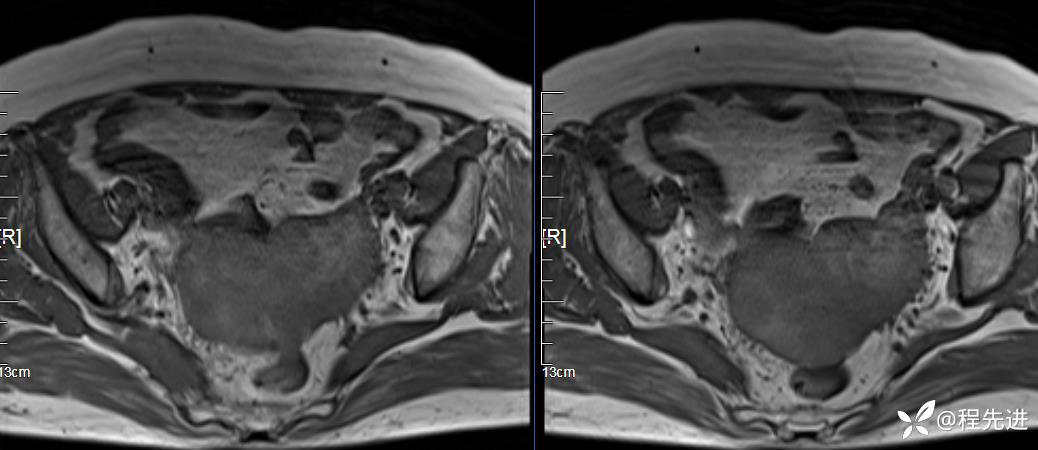

MRI平扫: